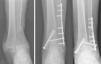

Tras nueva terapia intravenosa específica consistente en meropenem+linezolid, la paciente evoluciona satisfactoriamente con cicatrización de las heridas y desaparición de la úlcera, siendo dada de alta con antibioterapia oral (septrim Forte, un comprimido cada 24h). En último control, a los 9 meses de la intervención, la paciente está asintomática, con normalización de los reactantes de fase aguda, cicatrización de heridas y signos radiológicos de fusión tibiotalocalcánea, caminando con ayuda de una muleta, sin dolor, y compensando el acortamiento del miembro con un alza (fig. 4).